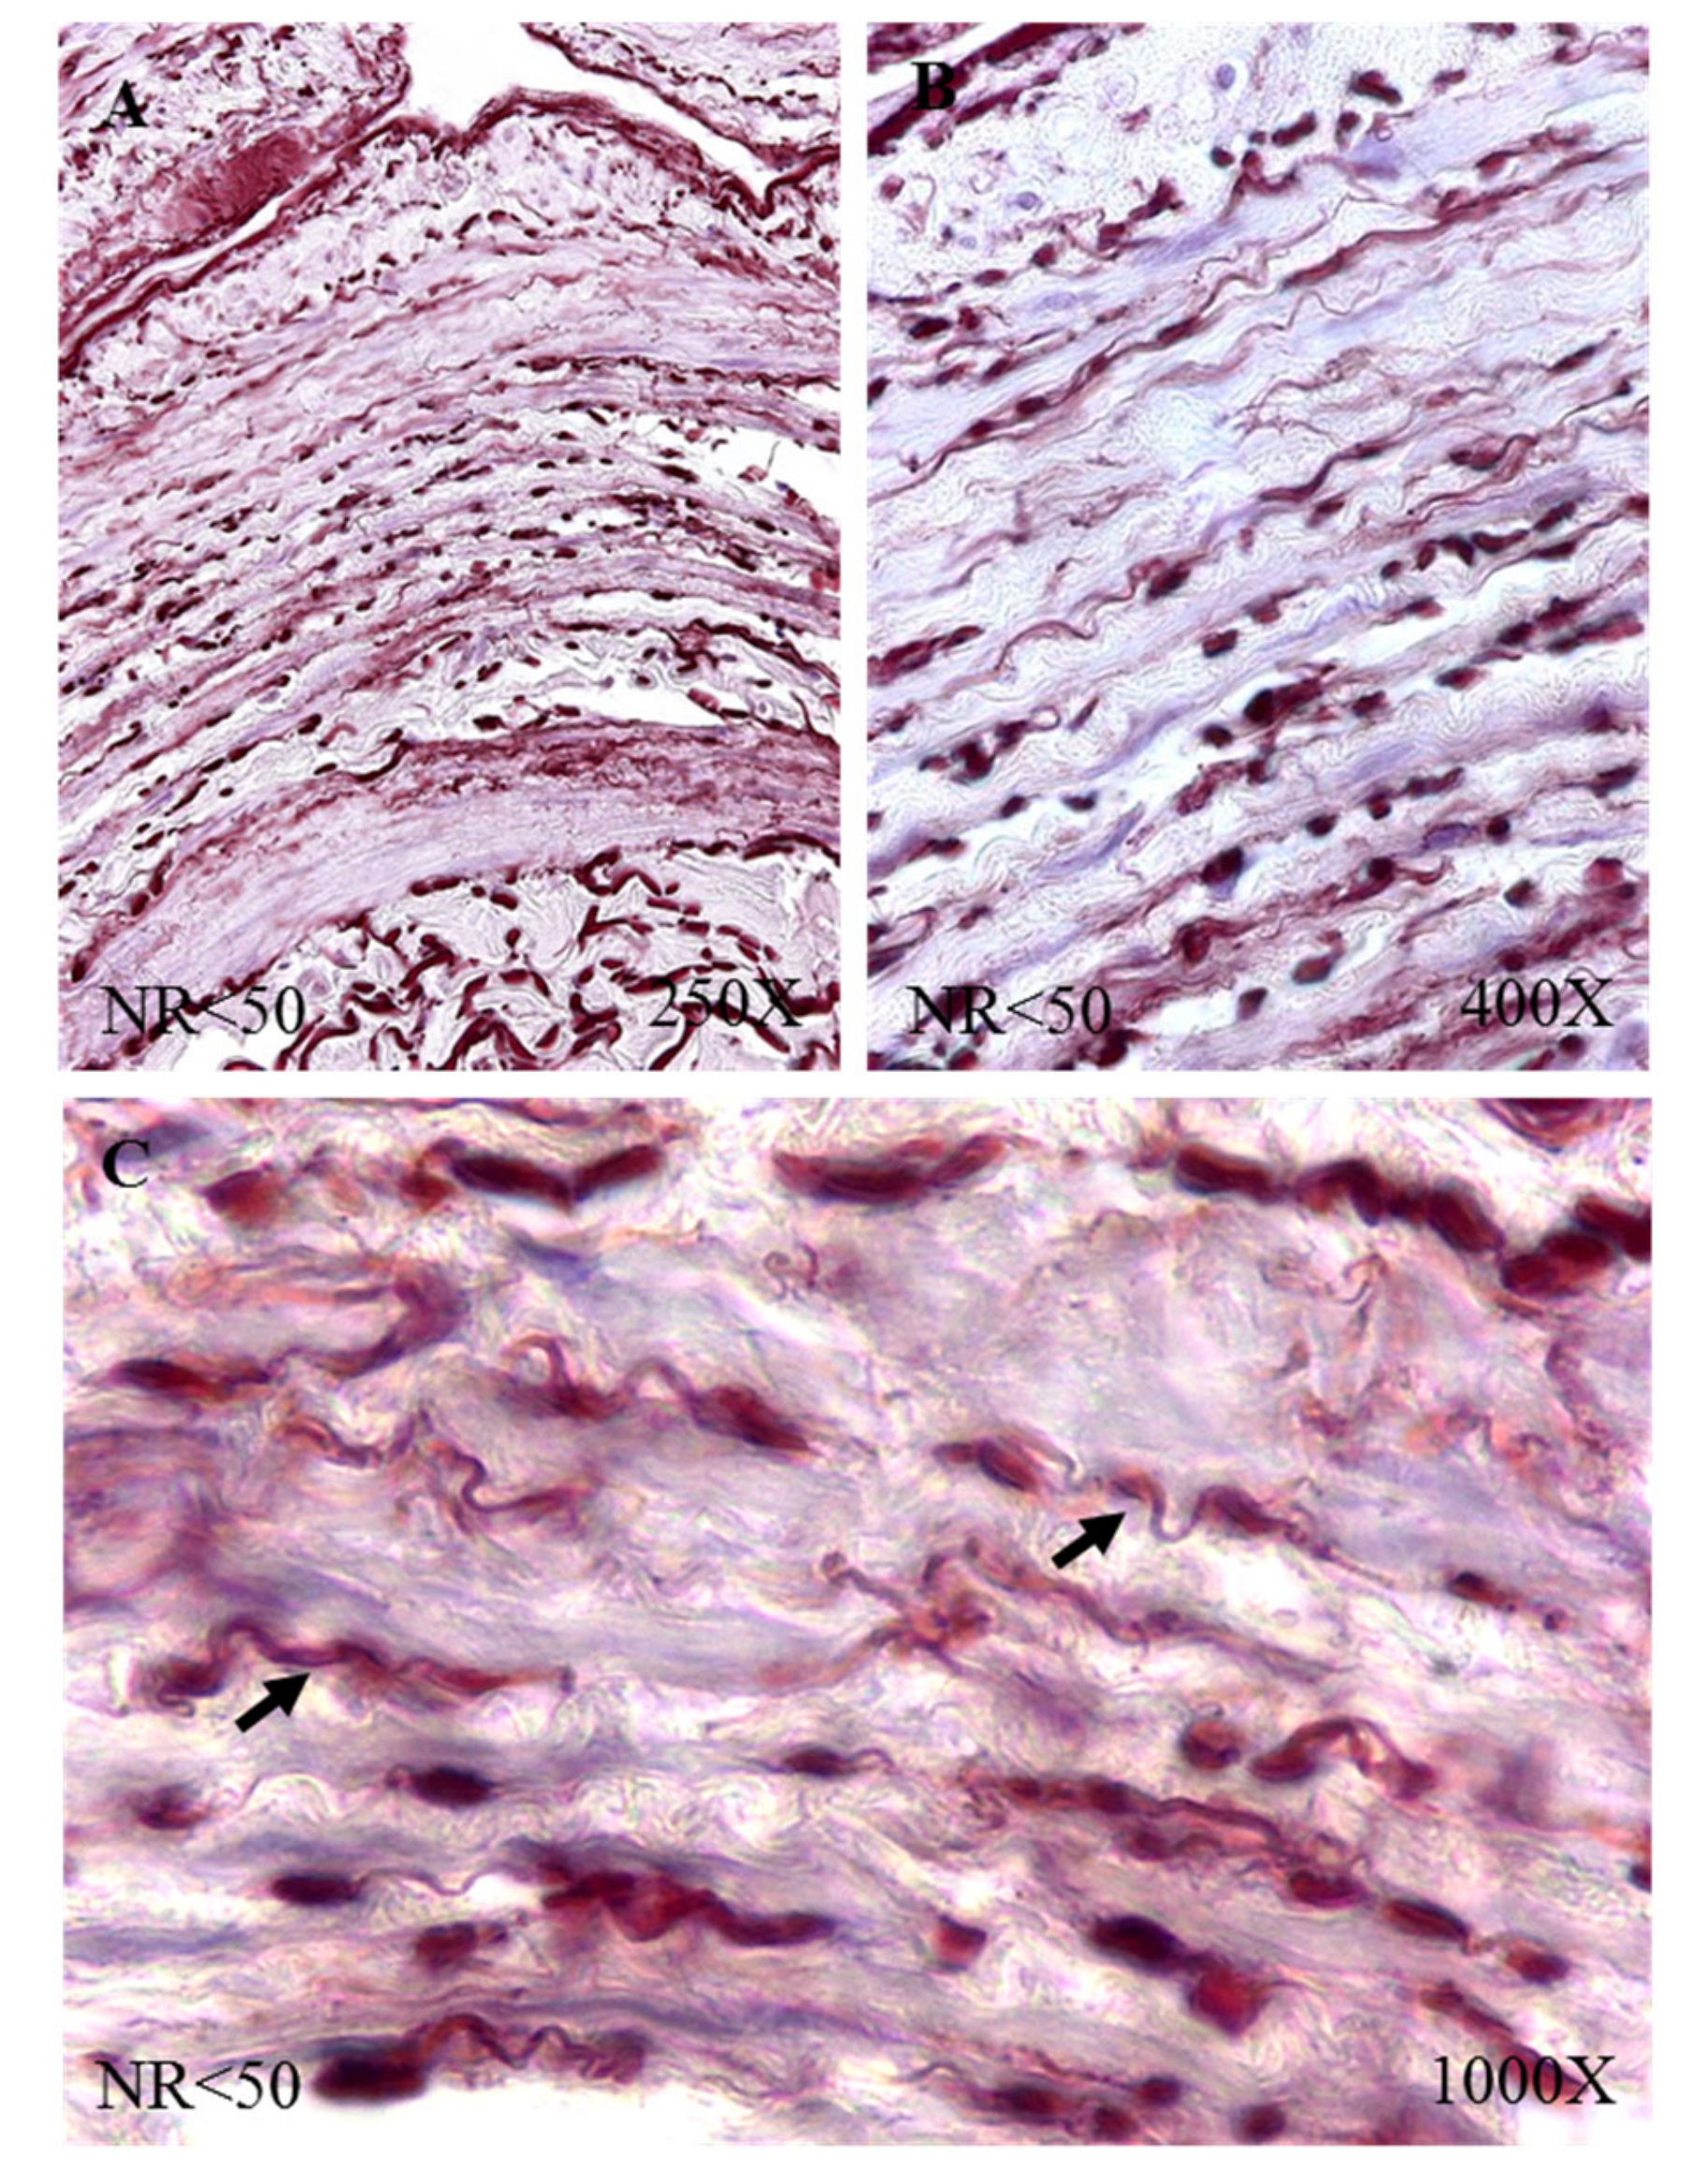

Figure 2. Images showing the elastic fibers in patients with NR < 50 (AC).

The study of the elastic component was carried out by visualizing the elastic fibers in tissue samples. This study revealed differences in the number of elastic fibers depending on the presence or absence of venous reflux and the age of the patients. In global terms, we observed how the R patients had a statistically significant decrease in the number of elastic fibers in the tunica media of the vein wall (Figure 1 and Table 4). Considering the age factor, it was possible to describe how the NR ≥ 50 and R < 50 have the highest number of elastic fibers that were statistically significant (Figure 1 and Table 4). This fact was kept in the intimal and adventitial tunics (Figure 1, Figure 2, Figure 3, Figure 4 and Figure 5 and Table 4).